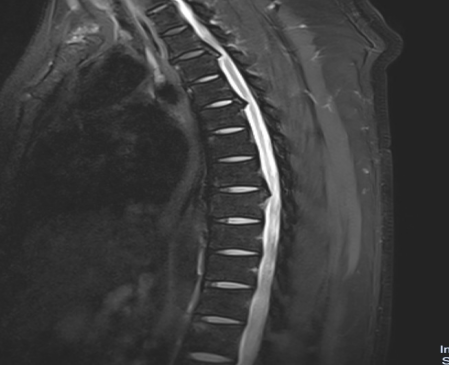

入院后,國(guó)文醫(yī)院骨科迅速組織多名專家會(huì)診,并為吳先生完善了頸椎及胸椎的 MRI 檢查。結(jié)果顯示,吳先生的頸椎及胸椎多階段嚴(yán)重椎管狹窄,脊髓壓迫超過(guò) 50%,情況十分危急。經(jīng)過(guò)骨科專家團(tuán)隊(duì)的綜合會(huì)診及評(píng)估,最終為他制定了一套個(gè)性化的治療方案,包括頸椎后路單開(kāi)門椎管減壓頸椎融合內(nèi)固定術(shù),以及胸椎間盤切除伴椎管減壓胸椎植骨融合內(nèi)固定術(shù)。在完善術(shù)前檢查、確認(rèn)無(wú)手術(shù)禁忌后,骨科主任呂國(guó)福如期為吳先生實(shí)施了手術(shù)。